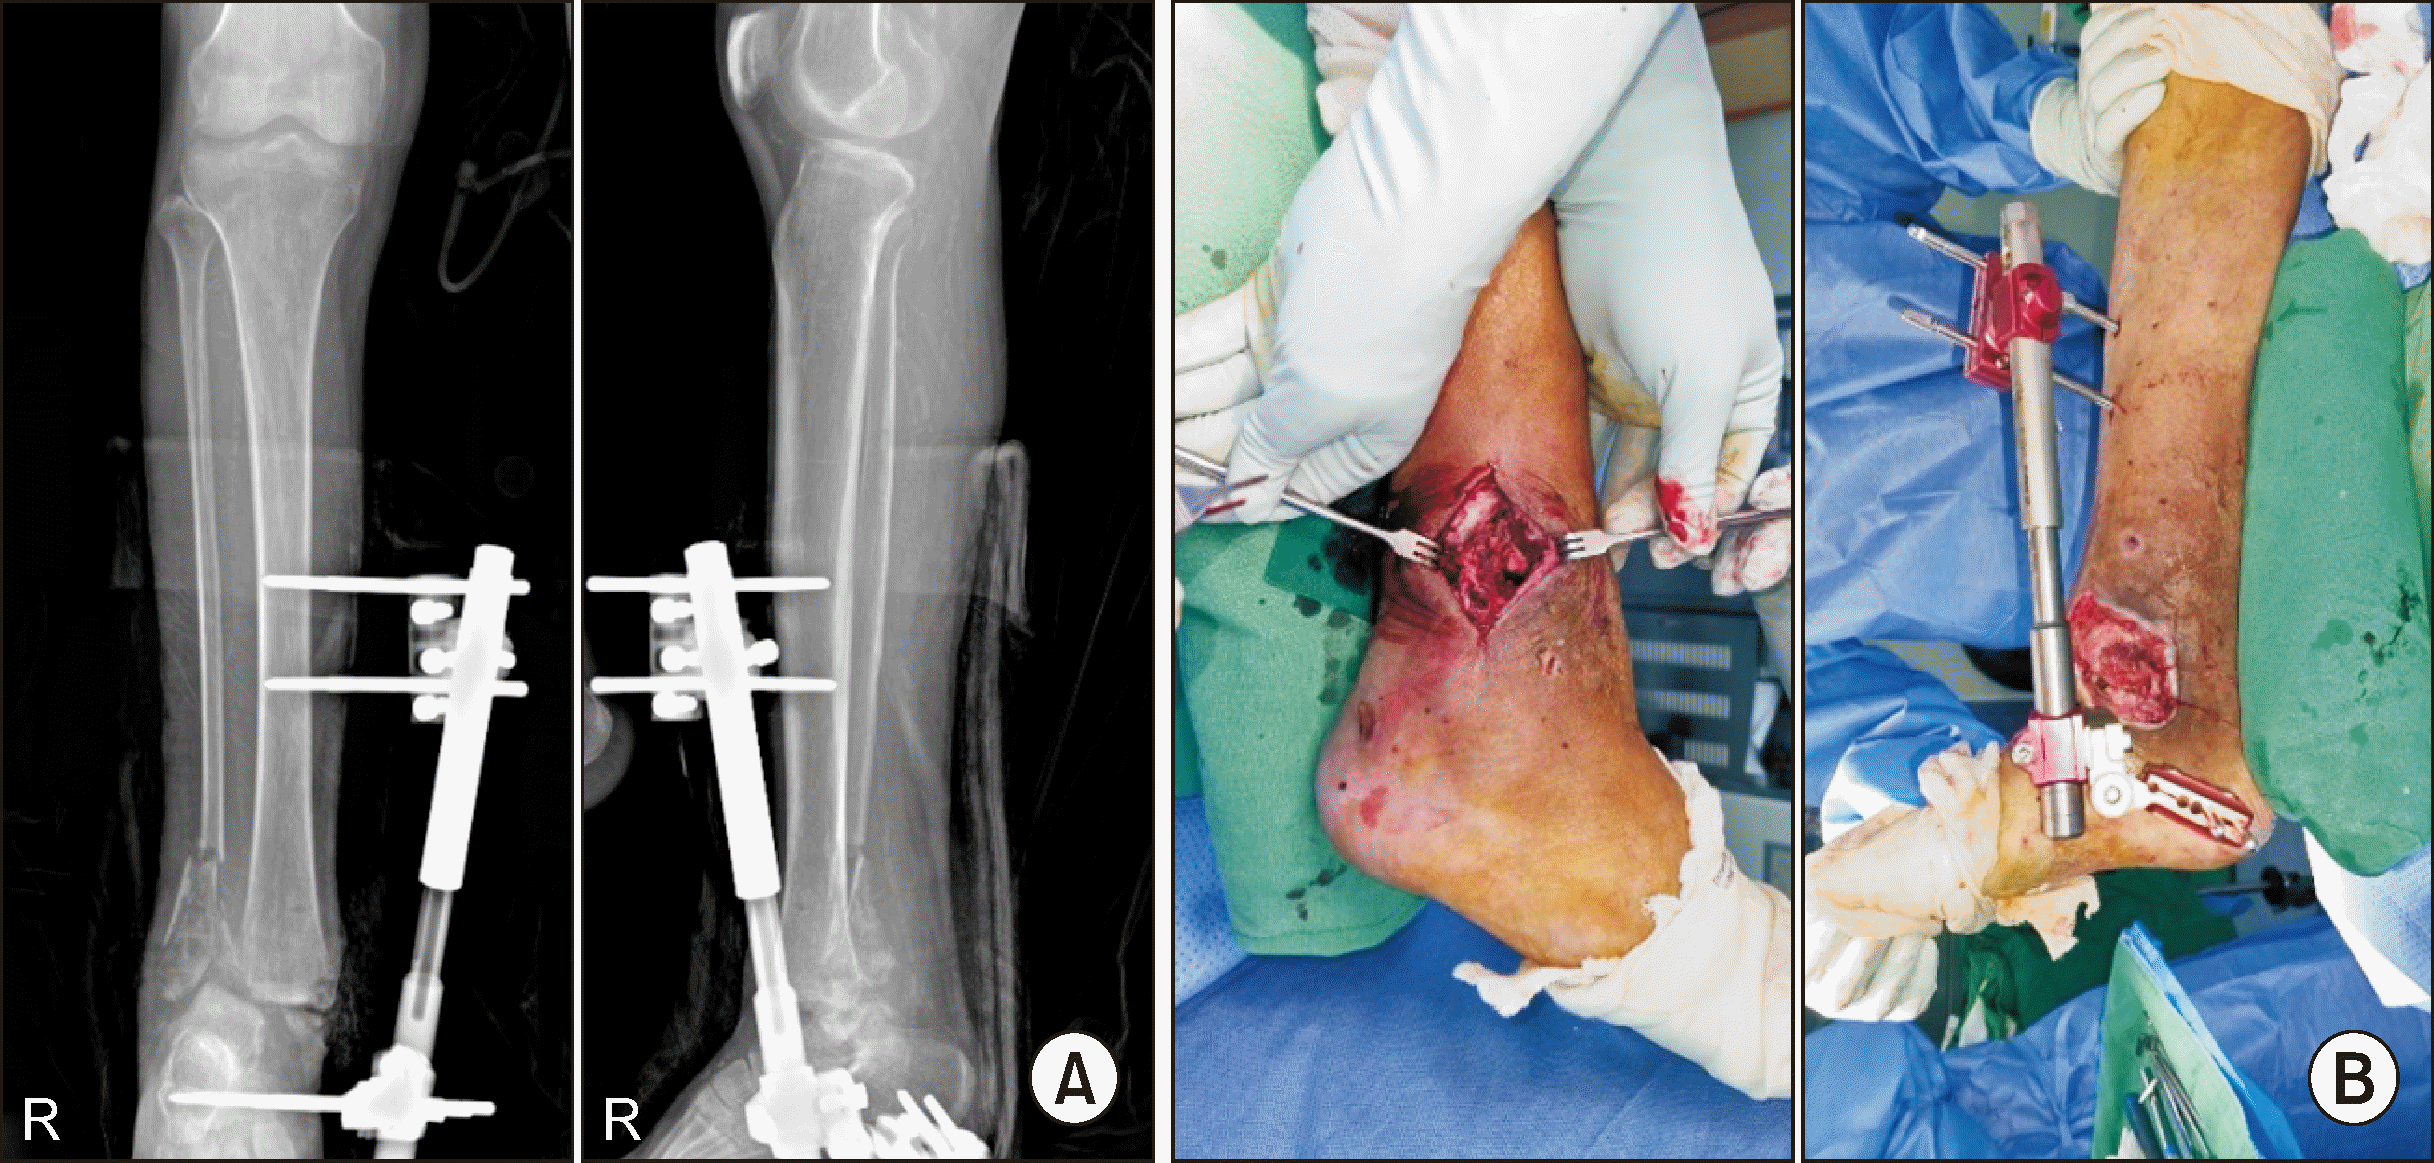

Subsequent imaging studies revealed non-union and lateral displacement of the fractures, prompting a revision OR/IF. The patient was also placed in isolation due to COVID-19, and further radiographs revealed metal failure and tibiotalar joint dislocation (Fig. 5). An implant-associated infection was confirmed, leading to subsequent procedures including metal removal, debridement, and the application of an external fixator (Fig. 6).

Figure 6

(A) Post-operative radiograph after applying external fixator for septic ankle findings. (B) Intra-operative clinical picture applying external fixator for septic ankle findings.

Figure 7

(A) Post-operative radiograph after tibiotalocalcaneal fusion using a retrograde T2 nail. (B) Clinical findings showing a medial wound defect at the time of surgery.